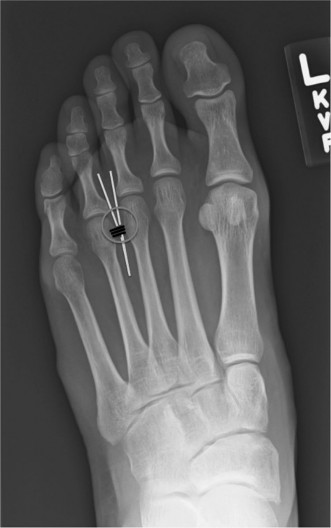

Figure 6: Postoperative radiograph demonstrating appropriate alignment after hallux valgus correction, including medial eminence resection and osteotomy, with stable fixation.

Distal Metatarsal Osteotomies (e.g., Chevron, Austin, Reverdin-Green): Used for mild to moderate deformities (IMA < 16-18°).

- A V-shaped or L-shaped cut is made in the metatarsal head or neck.

- The distal fragment (including the metatarsal head and articular surface) is translated laterally to reduce the IMA.

- Rotation can also be incorporated to address metatarsal pronation.

- Fixation is typically with a single screw, K-wire, or absorbable pin.

Figure 4: Intraoperative image demonstrating a distal metatarsal osteotomy (e.g., Chevron) with planned screw fixation. -